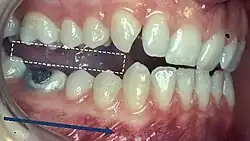

Canine Guidance

- Dynamic occlusion that occurs on the canines (on the working side) during lateral excursions of the mandible.

- These teeth are best suited to accept horizontal forces in eccentric movements due to their long roots and good crown/root ratio

Group Function

- Multiple contacts between the maxillary and mandibular teeth in lateral movements on the WS whereby simultaneous contact of several teeth acts as a group to distribute occlusal forces.

- It is preferable for this guidance to be as anterior as possible e.g. premolars rather than molars, as there is increased force applied when the contacts are closer to the TMJ.